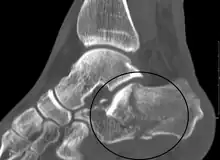

Conventional radiography is usually the initial assessment tool when a calcaneal fracture is suspected. Recommended x-ray views are (a) axial, (b) anteroposterior, (c) oblique and (d) views with dorsiflexion and internal rotation of the foot. However, conventional radiography is limited for visualization of calcaneal anatomy, especially at the subtalar joint. A CT scan is currently the imaging study of choice for evaluating calcaneal injury and has substituted conventional radiography in the classification of calcaneal fractures.[13] Axial and coronal views are obtained for proper visualization of the calcaneus, subtalar, calcaneocuboid and talonavicular joints.

The Angle of Gissane, or "Critical Angle", is the angle formed by the downward and upward slopes of the calcaneal superior surface. On a lateral radiograph, an angle of Gissane > 130° suggests fracture of the posterior subtalar joint surface. Böhler's angle, or the "Tuber Angle", is another normal anatomic landmark seen in lateral radiographs. It is formed by the intersection of 1) a line from the highest point of the posterior articular facet to the highest point of the posterior tuberosity, and 2) a line from the former to the highest point on the anterior articular facet. Böhler's angle is normally 25° to 40°.[14] It is named after Austrian physician Lorenz Böhler.[16] A decreased angle is indicative of a calcaneal fracture.